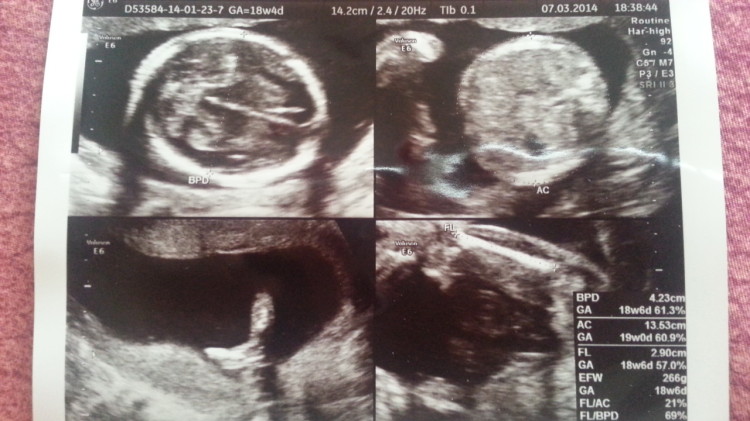

Last week we went to the obgyn and everything’s fine. Baby’s heartbeat is good at 155bpm and he’s growing well, just perfectly aligning with the normal curve. As of last week, the baby length was 13.53cm and weighted 266grams. Thanks to this growing baby, I have successfully gained 4.5kgs in 19 weeks. Well done indeed. Hahaha. Actually the last 3,5kgs I gained during my month in Australia. Never mind baby, as long as you’re healthy and strong, I don’t mind seeing an additional kilo on the scale. I don’t own a scale at home so hopefully it’s only another kilo each month. Teehee. One thing mommy and daddy never forget is to pray that you will continue to grow healthy and strong :)

ultrasound at 18 weeks and 4 days

Oh anyway, our obgyn had an 80% guess of our baby’s gender. We didn’t get a clear picture during the ultrasound because the baby was awake and moving when we did it so the doctor was only 80% sure. FYI, the doctor’s guess was the same as my initial gut feeling so I’m fairly sure that he’s right. Does anyone have a guess on what our baby’s gender might be based on this ultrasound?